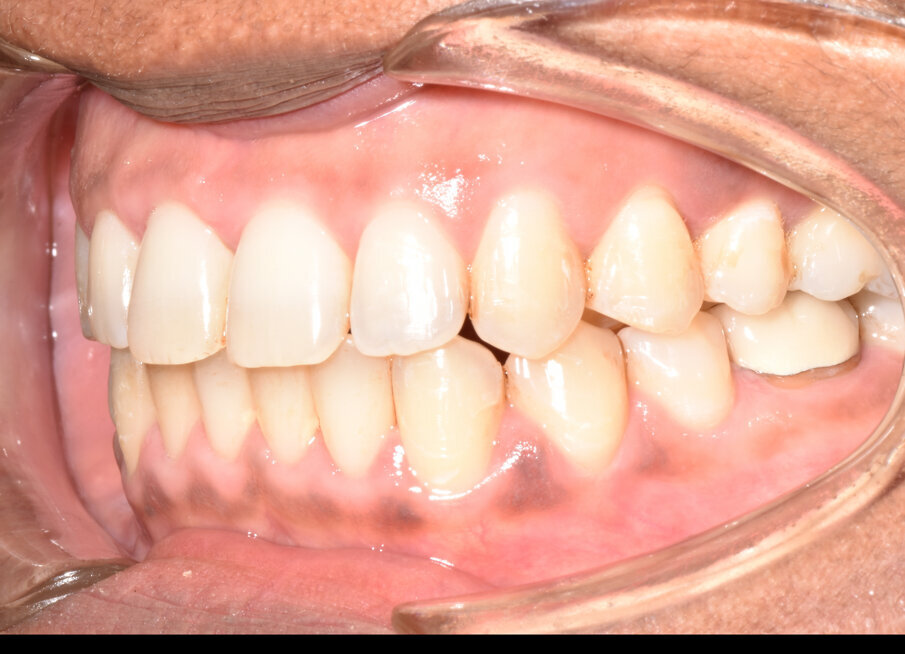

A 56-year-old female patient presented with a Class III malocclusion, anterior crowding and a 2-3 mm anterior open bite. Clinical photographs showed an ideal incisor display upon smiling. The panoramic film was unremarkable, and the lateral cephalometric film revealed a negative 1 mm overjet. (Figs. 1 to 10)

The treatment plan for this patient involved upper molar intrusion without the use of TADS in order to achieve counterclockwise rotation of the mandible and closure of the anterior open bite. Class III inter-arch elastics were prescribed to establish Class I molar and canine relationships and achieve proper overjet.

The 31-aligner Spark treatment concluded in five appointments over 7.75 months of active treatment without the need for TADS or refinement aligners. The patient’s excellent compliance was an important factor in the results achieved. Post-treatment photographs demonstrate correction of her Class III, crowded, anterior open bite malocclusion. (Figs. 16-23)